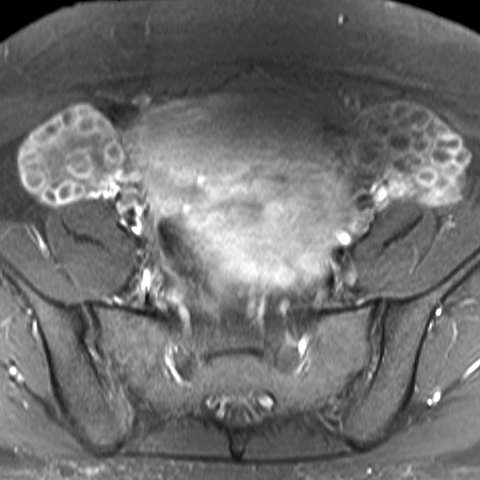

28 year old female with excessive hair growth on her face and abdomen presents with irregular vaginal bleeding. [2 of 2]